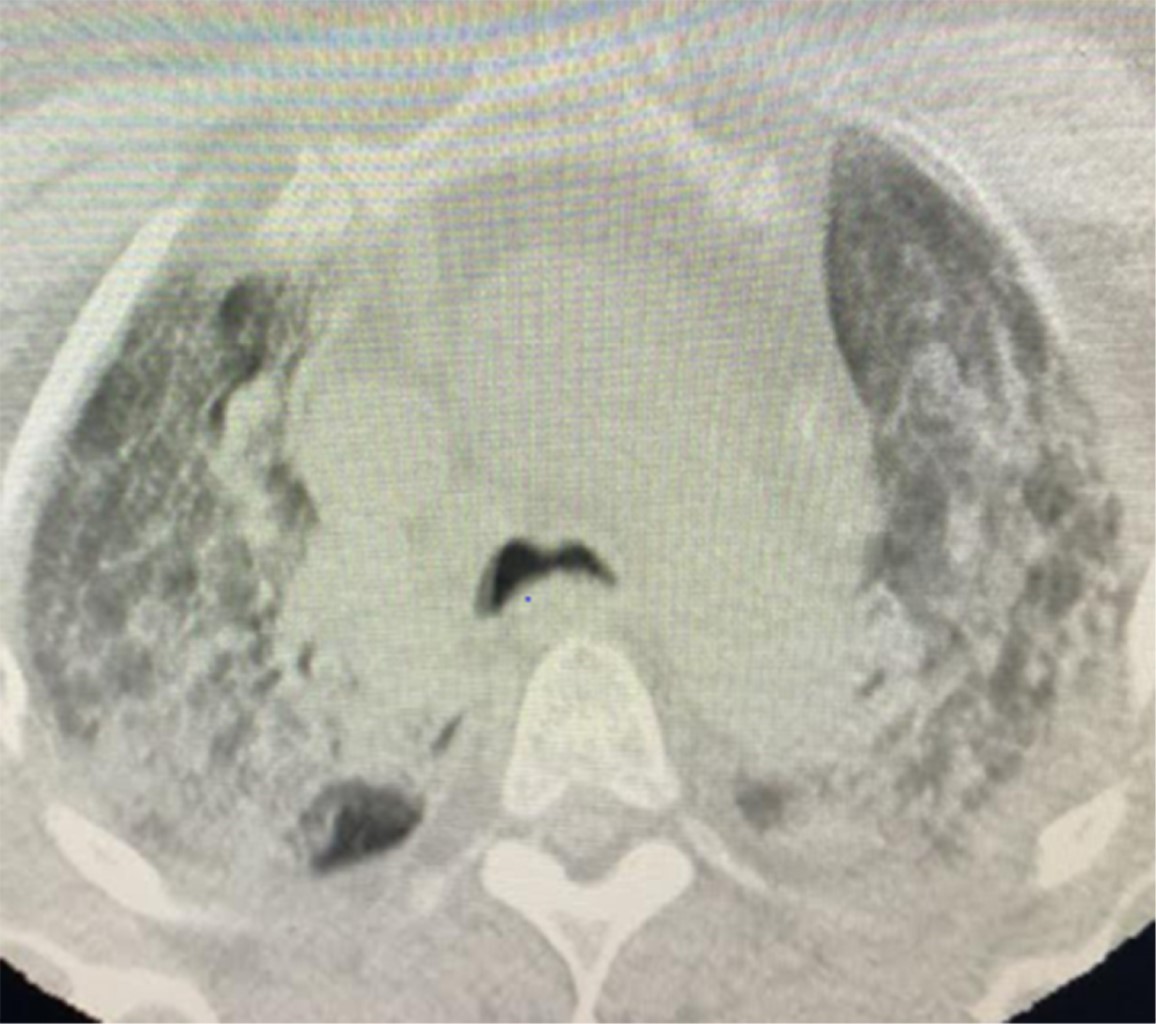

Figure 2